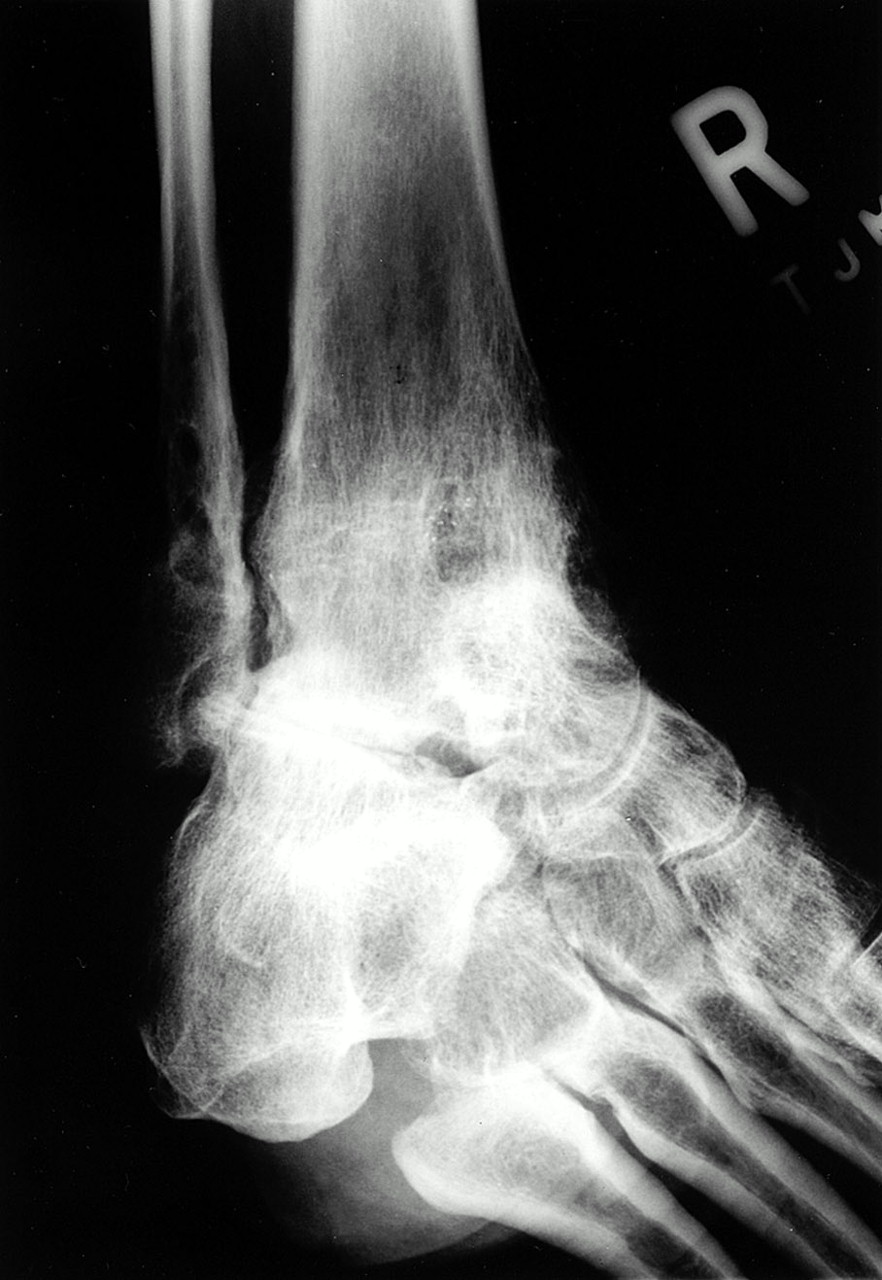

| Isherwood imagen |

La proyección se realiza con el paciente en decúbito supino con rodilla a 90º de flexión, tobillo a 90º de flexión dorsal. Pie sobre el chasis de rayos y sobre una cuña de 45º para la rotación interna o simplemente con la rotación interna de 45 º. El rayo irá dirigido perpendicular al chasis centrado sobre el seno de tarso, a 2 cm anterior y distal al maleolo externo o peroneo.

| Imagen radiográfica Isherwood |